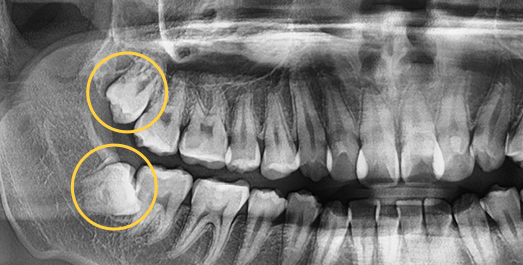

Some wisdom teeth erupt normally, but others may erupt at an angle, horizontally, or remain fully impacted. Wisdom teeth that do not erupt properly can disturb the dental arch and are difficult to clean, which may lead to decay of adjacent molars. In such cases, extraction is recommended.

Complex wisdom tooth cases, Seoul The Nature Dental Clinic

does not give up.

Using 3D CT, we evaluate the shape of the wisdom tooth, its roots, and surrounding nerves to support a safer extraction process.